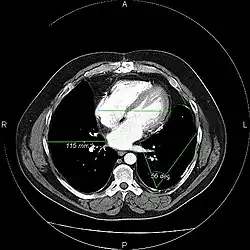

The same image following contrast adjustment, sharpening and measurement tags added by the system

A picture archiving and communication system (PACS) is a medical imaging technology which provides economical storage and convenient access to images from multiple modalities (source machine types).[1] Electronic images and reports are transmitted digitally via PACS; this eliminates the need to manually file, retrieve, or transport film jackets, the folders used to store and protect X-ray film. The universal format for PACS image storage and transfer is DICOM (Digital Imaging and Communications in Medicine). Non-image data, such as scanned documents, may be incorporated using consumer industry standard formats like PDF (Portable Document Format), once encapsulated in DICOM. A PACS consists of four major components: The imaging modalities such as X-ray plain film (PF), computed tomography (CT) and magnetic resonance imaging (MRI), a secured network for the transmission of patient information, workstations for interpreting and reviewing images, and archives for the storage and retrieval of images and reports. Combined with available and emerging web technology, PACS has the ability to deliver timely and efficient access to images, interpretations, and related data. PACS reduces the physical and time barriers associated with traditional film-based image retrieval, distribution, and display.